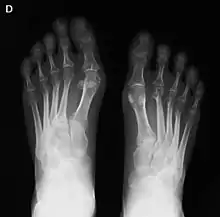

La artritis o inflamación de las articulaciones es la manifestación fundamental de la artritis reumatoide. Las articulaciones afectadas están hinchadas, calientes, dolorosas y rígidas, en especial al levantarse por la mañana o tras el reposo prolongado. Al principio pueden estar afectadas solo una o varias articulaciones, pero progresivamente se van sumando más articulaciones inflamadas —poliartritis—, siendo las que con más frecuencia se afectan las pequeñas articulaciones de las manos y los pies, aunque también es frecuente la afectación de otras articulaciones más grandes como los codos, los hombros, las rodillas o los tobillos.[48] La rigidez matinal es, con frecuencia, un dato destacado de la enfermedad y suele durar más de una hora. Estos datos ayudan a distinguir a la artritis reumatoide de otros problemas no inflamatorios de las articulaciones, como la artrosis u otros tipos de artritis. Las articulaciones se afectan habitualmente de un modo simétrico —afectando articulaciones semejantes en ambos lados del cuerpo—.[49] A medida que la enfermedad progresa, la inflamación articular causa erosiones y destrucción de las superficies articulares y daños tendinosos. Los dedos de las manos pueden sufrir diversas deformidades dependiendo de qué articulaciones y estructuras son las más lesionadas. Son deformidades típicas de la artritis reumatoide evolucionada los dedos en cuello de cisne, la deformidad en ráfaga cubital, la deformidad en boutonniere y el pulgar en Z.[48] La inflamación articular mantenida puede originar daños estructurales en las articulaciones, causando deformidad y pérdida funcional de la articulación afectada.[50][51]

La radiografía convencional es la técnica de imagen estándar de la artritis reumatoide. Los primeros signos radiológicos son la osteoporosis yuxtaarticular y el aumento de partes blandas. Estos cambios se siguen de la disminución del espacio articular, que corresponde a la pérdida de cartílago articular, y la aparición de erosiones óseas en las zonas adyacentes al cartílago articular. El tiempo mínimo para la detección de cambios estructurales en las radiografías está entre 6 y 12 meses, detectándose erosiones radiológicamente en el 50% de los pacientes en el primer año de la enfermedad.[49] En la práctica clínica se utilizan las radiografías para el diagnóstico de la enfermedad, para valorar la gravedad del daño articular y para evaluar su progresión. El ultrasonido y la resonancia magnética son técnicas más sensibles que la radiología convencional.